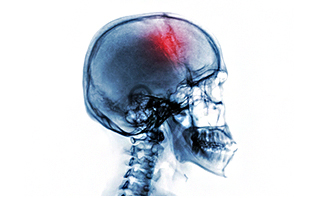

颅骨缺损是由外力导致颅骨缺损,从而引发的一些症状的疾病,颅骨缺损的症状挺多,有的患者会出现恐惧心理,对外界事物的排斥,其影响很大,要及早治疗才是对患者健康的负责。那么颅骨缺损的症状有哪些呢?

颅骨缺损的症状:

一、颅骨缺损小于3cm者:

通常颅骨缺损小于3cm者多无症状,施行颞肌下减压术或枕下减压术后,有肥厚的肌肉及筋膜覆盖并在缺损区可以形成坚韧的纤维性愈合层,起到原有颅骨对脑的保护作用,在临床上亦无任何症状。

二、直径3cm以上的缺损:

特别是位于额部有碍美观和安全的缺损,常有这样或那样的症状。